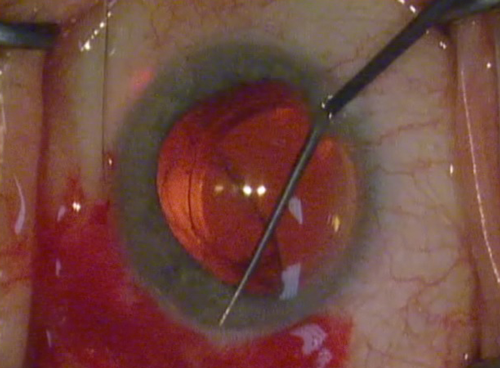

Figure 2: Kahook dual blade is designed to remove trabecular

meshwork ab-internally under gonioscopic guidance.

Trabecular meshwork bypass / removal

It has been well demonstrated that increased trabecular meshwork resistance is a contributing factor to increased IOP [8]. Trabecular meshwork removal, by way of goniotomy or Trabectome has demonstrated significant IOP reduction [9]. The Kahook Dual Blade (New World Medical, Rancho Cucamonga, CA) has been designed to simulate trabectome surgery by ab-internally removing TM over the same three to four clock hours (Figure 2). It is a single use device that makes parallel incisions in the TM and inner wall of Schlemm’s canal and is far cheaper and simpler than the Trabectome. However, it does not provide any anterior chamber stability and does not provide suction. A pre-clinical study demonstrated that the KDB blade removed TM more thoroughly and with less collateral damage than a simple MVR blade or Trabectome [10].

There have been no published results in the literature of ab-interno trabeculotomy performed with the KDB blade as yet. In-vitro whole eye perfusion studies suggest promising pressure lowering [10], albeit without assessing the in-vivo risk of intraoperative hyphaema.